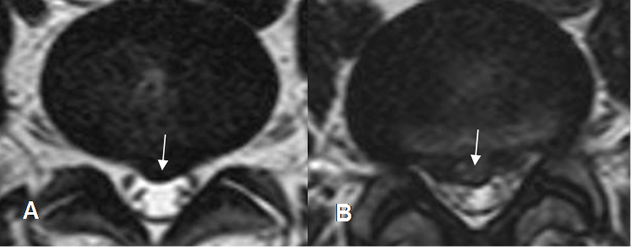

Fig 99. Hernia paramediana.

A y B: TAC axial. Imágenes con densidad de tejidos blandos que ocupan el receso lateral, comprimen las raíces nerviosas y corresponden a hernias paramedianas.

Fig 100. Hernia paramediana.

A y B: RM axial en T2. Imágenes con densidad de tejidos blandos que ocupan el receso lateral, comprimen las raíces nerviosas y corresponden a hernias paramedianas.